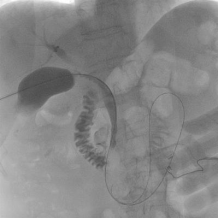

术中在超声实时引导下进 通过Seldinger技术建立胆囊、胆总管

行胆囊精准穿刺 至十二指肠的手术通道

2. 分步施治,直击病灶:建立稳定的经胆囊通道后,团队便拥有了直达病所的“工作隧道”。

★针对结石患者:团队沿通道进入胆总管,利用球囊扩张十二指肠乳头括约肌,巧妙运用网篮或球囊将结石顺利推入十二指肠,实现了微创取石。该技术的另一大优势在于,它通过球囊扩张十二指肠乳头括约肌,是一种可恢复的、非破坏性的操作,完美避免了腹腔镜或内镜下括约肌切开术可能造成的永久性损伤。由于括约肌的生理功能得以保留,从长远看,术后因肠液反流导致的胆道感染并发症也得以有效避免。该方法避免了传统开腹手术的大创伤,也弥补了内镜逆行的不足。